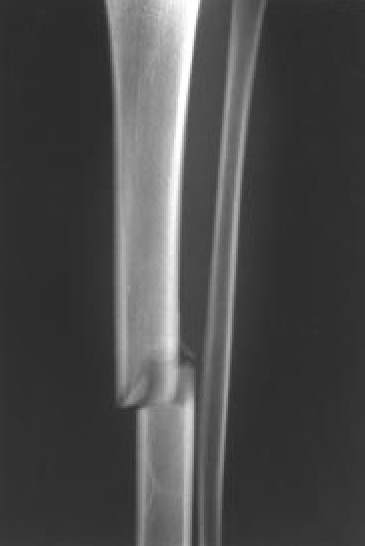

Fig. 9A.: Fractura de la diáfisis tibial